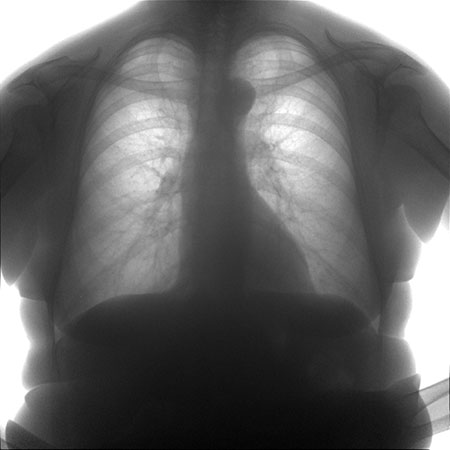

| Рентгенография грудной клетки | Изменения формы и размера аорты, кальцификация аорты | Диагностический метод, не используется для лечения |

Уплотнение дуги аорты можно выявить с помощью флюорографии, поэтому регулярное прохождение этого обследования играет важную роль в профилактике заболеваний.

Флюорографический снимок, на котором видно изменение структуры кровеносного сосуда с кальцинированными участками, может свидетельствовать о начале атеросклероза.